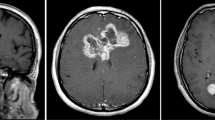

Multimodal medical imaging (MMI) volumes can be derived by spatial correlating intensity distributions from a number of different diagnostic volumes with complementary information. An unsupervised approach to MMI volumes segmentation is recommended by many authors. Due to complexity of the data structure, this kind of segmentation is a very challenging task, whose main step is clustering in a multidimensional feature space. The partial volume effect originated by the relatively low resolution of sensors produces borders not strictly defined between tissues. Therefore memberships of voxels in boundary regions are intrinsically fuzzy and computer assisted unsupervised fuzzy clustering methods turn out to be particularly suited to handle the segmentation problem. In this paper a number of clustering methods (HCM, FCM, MEP-FC, PNFCM) have been applied to this task and results have been compared.